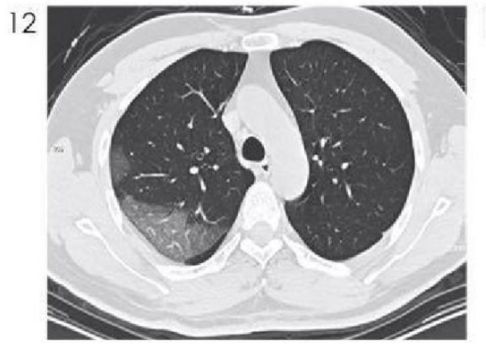

很多疾病都会出现结节,但是此次的新冠肺炎常出现磨玻璃结节、混合磨玻璃结节、实变结节,这在普通的肺炎中并不常见。

下面这个是新冠肺炎的磨玻璃结节影。有学者说这是斑片状阴影,我看着更像结节。

图12